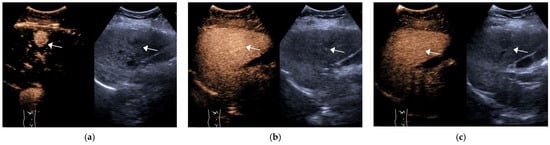

| Group | Num. | Enhancement Pattern in AP | Degree of Wash-Out | Time to Wash Out/s | ||||||

| Non-Rim APHE | Rim APHE | Non APHE | Mild | Marked | Non | <60 | ≥60 | Non-Wash Out | ||

| HCC | 61 | 58 (95.1%) | 2 (3.3%) | 1 (1.6%) | 54 (88.5%) | 3 (4.9%) | 4 (6.6%) | 11 (18.0%) | 46 (75.4%) | 4 (6.3%) |

| OM | 38 | 14 (36.8%) | 22 (57.9%) | 2 (5.3%) | 13 (34.2%) | 25 (65.8%) | 0 (0%) | 32 (84.2%) | 6 (15.8%) | 0 (0%) |

| X2/t | - | 40.745 | 43.373 | 41.946 | ||||||

| p | - | <0.001 | <0.001 | <0.001 | ||||||